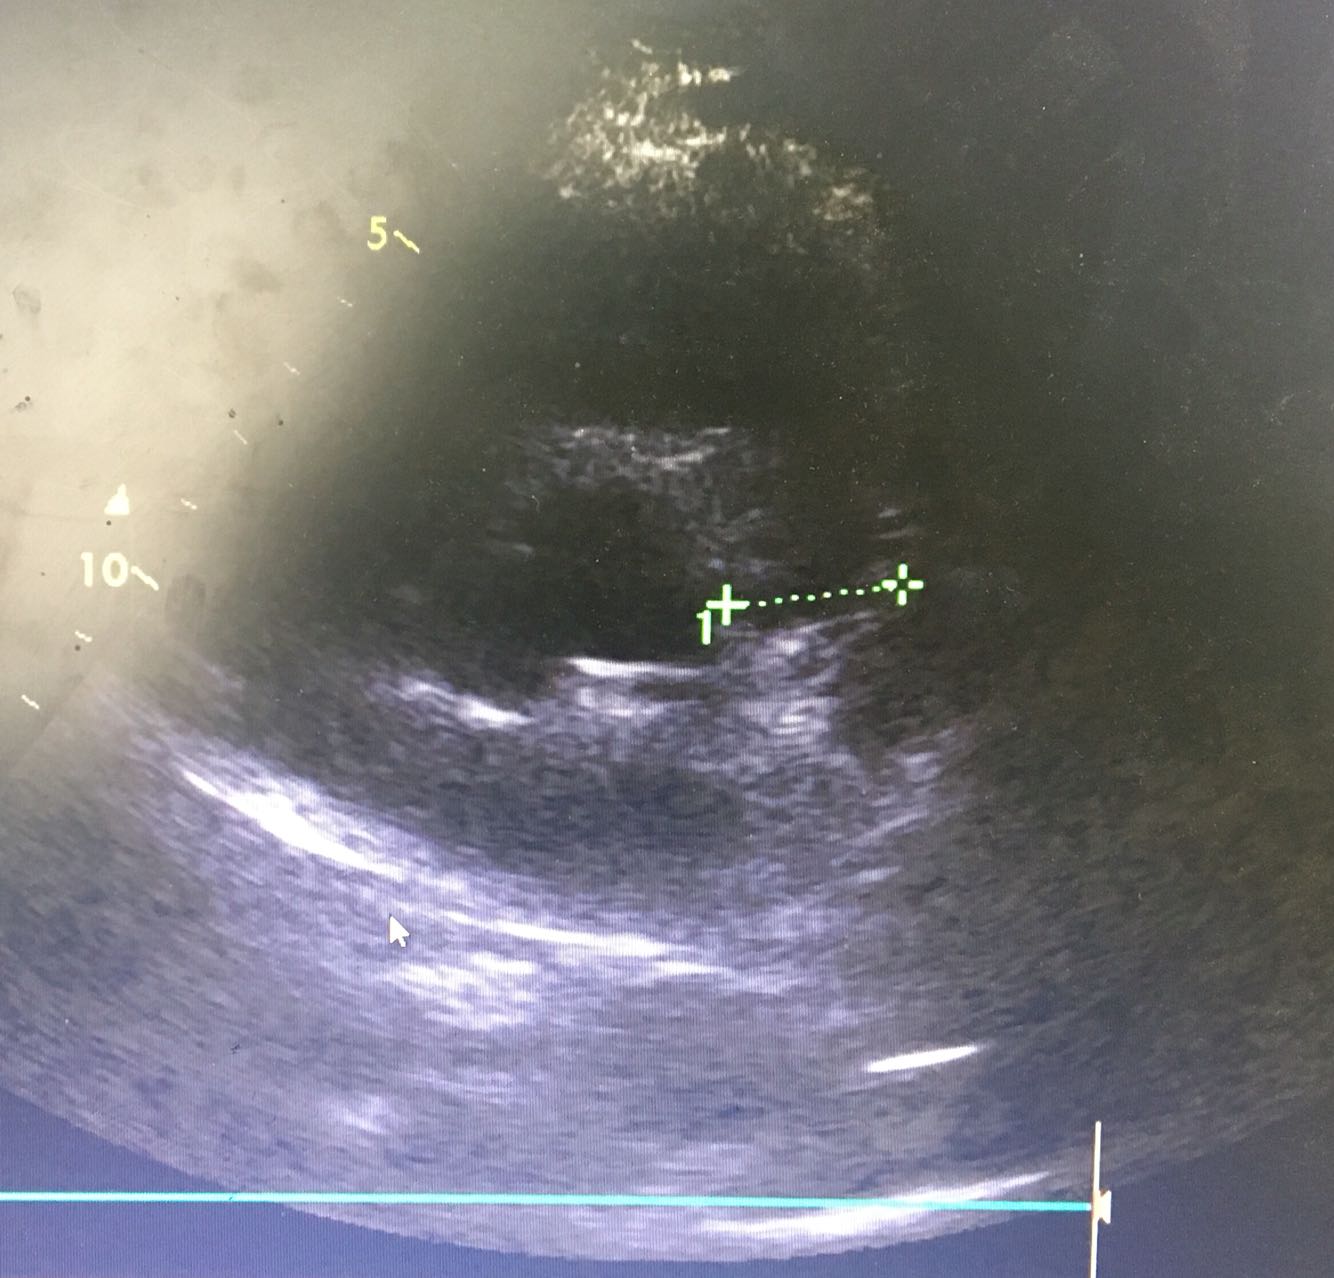

查体:神清,气平,BP:107/68mmHg,听力差,对答切题,双侧瞳孔等大等圆,直径3mm,对光反射存在,皮肤及巩膜无黄染,无贫血貌,浅表淋巴结未及肿大,颈软,气管居中,双肺呼吸音清,未及干湿罗音,心率90次/分,律齐,无杂音,腹平软压痛及反跳痛,未及明显肿块,肝肾叩击痛(-),移动性浊音阴性,双足背动脉搏动可及,双下肢无水肿,右足中趾红肿,神经系统检查(-) 辅助检查:血常规 HB99g/L,WBC2.7×10^9/L,RBC218×10^9/L, 免疫指标:IgA  <7mg/dl、IgG 2010mg/dl  IgM 50 mg/dl  叶酸:>24.8 ↑ng/ mL       维生素B12<50 ↓ pg/mL 甲状腺功能、肝肾功能、肿瘤指标、自身免疫指标、感染指标未见明显异常, 心脏超声:左房肥大 腹部B超:肝脏可见低密度病灶,左肾稍低密度灶,左肾盏可见小结石,余未见异常 盆腔CT:右下腹肠系膜多发小淋巴结显示,余未见异常